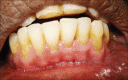

Gingival recession is defined as the apical migration of the gingival margin with exposure of root surfaces. The etiology of the condition is multifactorial. Given the high rate of gingival recession defects among the general population, it is imperative that dental practitioners have an understanding of the etiology, complications and management of the condition. A recent innovation in dentistry is the preparation and use of platelet-rich fibrin (PRF) for recession defects. The article presents a case report, which highlights the use of lateral sliding bridge flap along with PRF in a collagen membrane carrier (guided tissue regeneration) for the treatment of multiple recession defects.